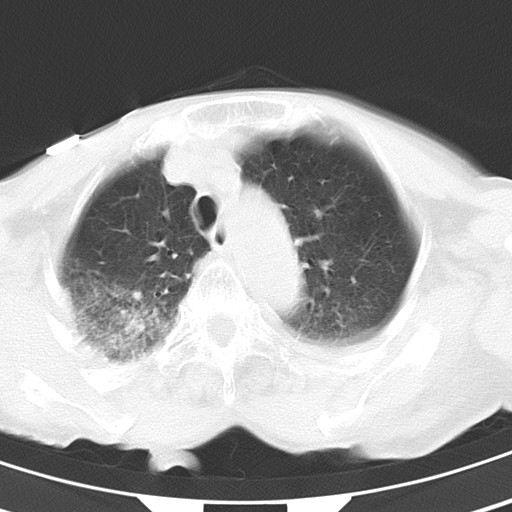

标题: CT21467:女,93岁,摔伤后检查。

女,93岁,摔伤后检查。

右肺炎症,心功能不全伴双侧胸腔积液,右下肺膨胀不全,食管裂孔疝,冠脉钙化,心包少量积液,左侧肋骨骨折,请上传骨窗.

双肺感染合并双侧胸腔积液、胸膜增厚粘连,骨性胸廓未见明确骨折征。

右侧锁骨\\肩胛骨骨折、右侧湿肺,心功能不全伴双侧胸腔积液,右下肺膨胀不全,左膈破裂或食管裂孔疝,冠脉钙化,心包少量积液,请上传骨窗.

右肺炎症,心功能不全伴双侧胸腔积液,右下肺膨胀不全,食管裂孔疝,冠脉钙化,心包少量积液,左侧肋骨骨折,右肩甲骨粉碎性骨折。93岁,高寿哇!

右肺炎症,心功能不全伴双侧胸腔积液,右下肺膨胀不全,食管裂孔疝,冠脉钙化,心包少量积液,左侧肋骨骨折,右肩甲骨粉碎性骨折。